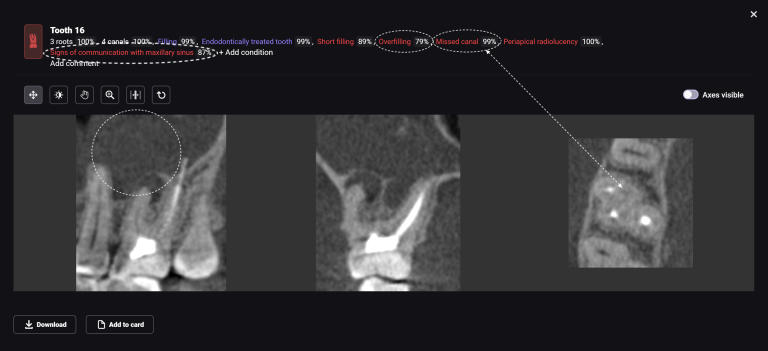

A cross-sectional radiological report created by Diagnocat AI allows the clinician to detect a subgingival calculus and make an accurate prognosis of each tooth before starting any complex treatment, whilst taking into account all of the endodontic, periodontal and functional criteria.